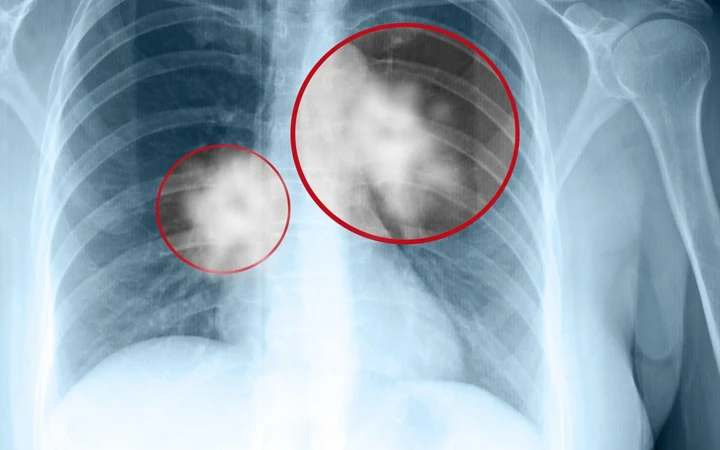

Bé trai 12 tuổi “phổi trắng xóa” chỉ sau 1 ngày mắc cúm: Cách phát hiện sớm cúm nặng ở trẻ

Một bé trai 12 tuổi nhiễm cúm A chủng H3N2, chỉ sau 24 giờ hình ảnh phổi đã xuất hiện tình trạng viêm lan tỏa nghiêm tRead More…